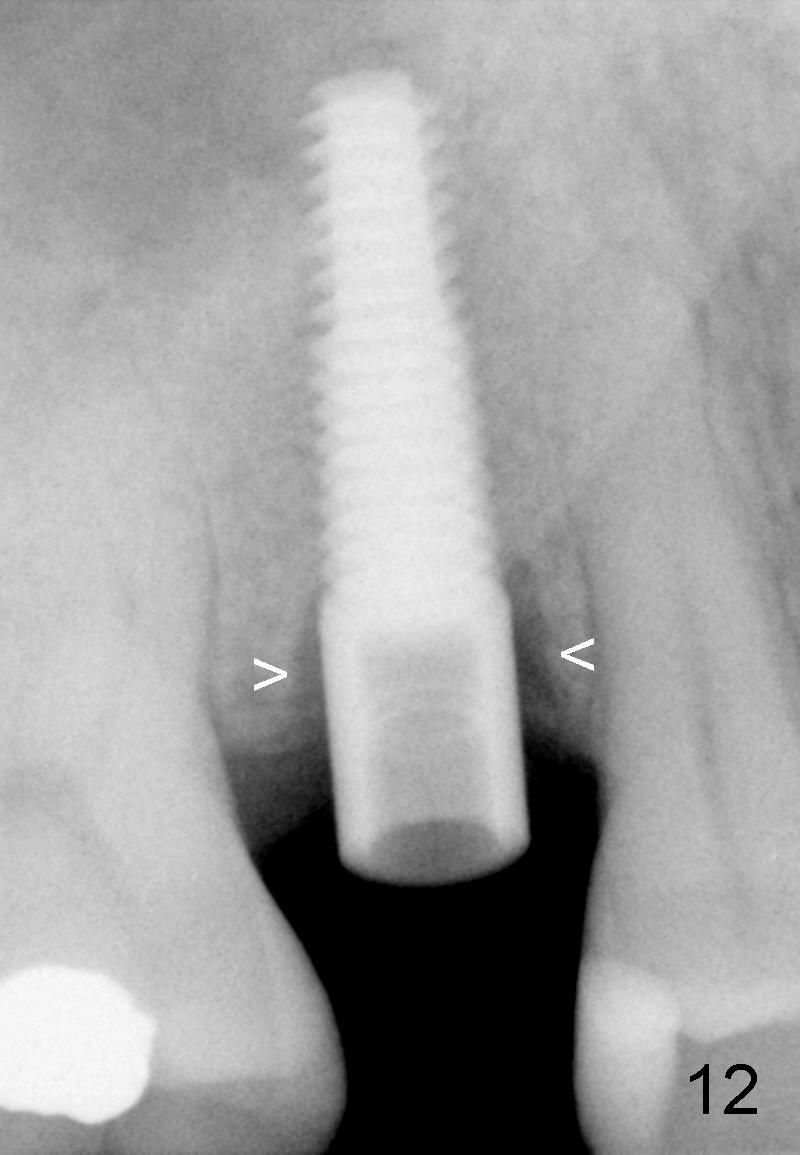

X-ray at 2.5 months postop shows crestal bone loss (Fig.12 *), although the implant is stable without inflammation (Fig.13 C: healing cuff). When the crown is bonded 3.5 months postop, there is no papilla (Fig.14 *).